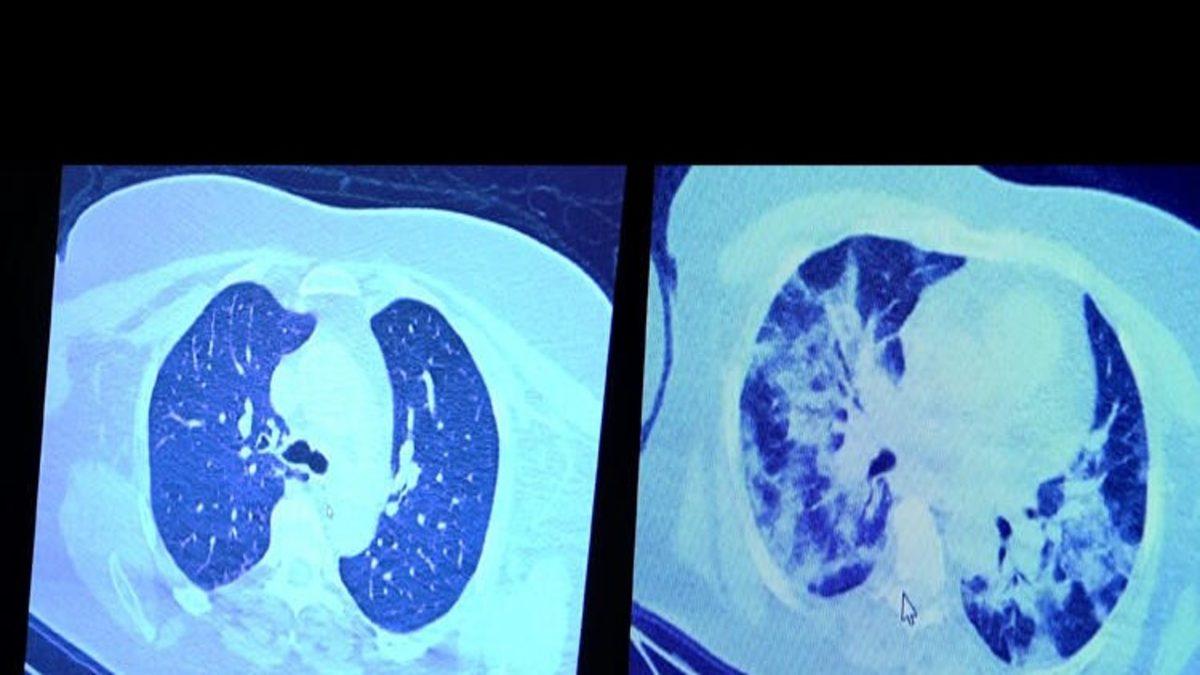

Özel bir hastanede görev alan Şevket Özkaya, durumun ciddiyetini bir hastanın akciğer filminden yola çıkarak dile getirdi. Özkaya, 55 yaşındaki bir hastanın hastaneye ilk geldiğinde çekilen akciğer tomografisi sonucunda, virüsün ciğerlere ciddi bir şekilde tutulum göstermediğini dile getirdi.

“Hastamız 55 yaşında olduğu için her an ilerleyebilir korkusuyla Sağlık Bakanlığımızın önerdiği ilaçları ve reçeteyi hastanemizden kendisine verdik.” ifadelerinde bulunan profesör, daha sonra hastanın ilaçları reddettiğini öğrendiğini dile getirdi. Aynı hasta, 1 hafta sonra solunum yetmezliği sebebi ile tekrar acile gelmiş ve yukarıdaki fotoğraftan anlaşılacağı üzere, çekilen tomografide virüsün akciğerleri tamamen sardığı ve büyük bir harabiyet yaşandığı gözlemlenmiş. Özkaya, solunum yetmezliği sebebiyle hastanın yoğun bakıma alındığını dile getirdi.

“Virüs enfekte ettikten bir süre sonra akciğerlerde yaygın buzlu camlara ve konsolidasyona neden oluyor”

Özkaya ilaçların önemini vurgulamak adına şu ifadeleri kullandı; "Ailenizi ve toplumu seviyorsanız kurallara uyun ve bakanlığımızın önerdiği tedavilerden kaçınmayın diyoruz. Çünkü virüs enfekte ettikten bir süre sonra akciğerlerde yaygın buzlu camlara ve konsolidasyona neden oluyor.”